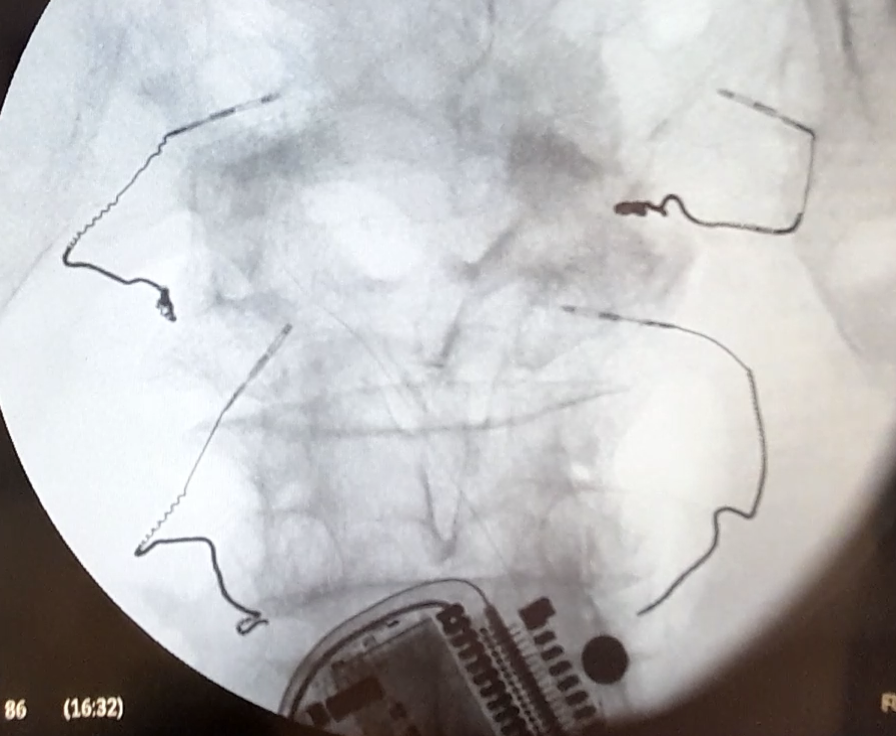

Figure 7 Handshake adapter models with the ability to connect to 2 or 4 Injectrodes shown in preclinical testing.